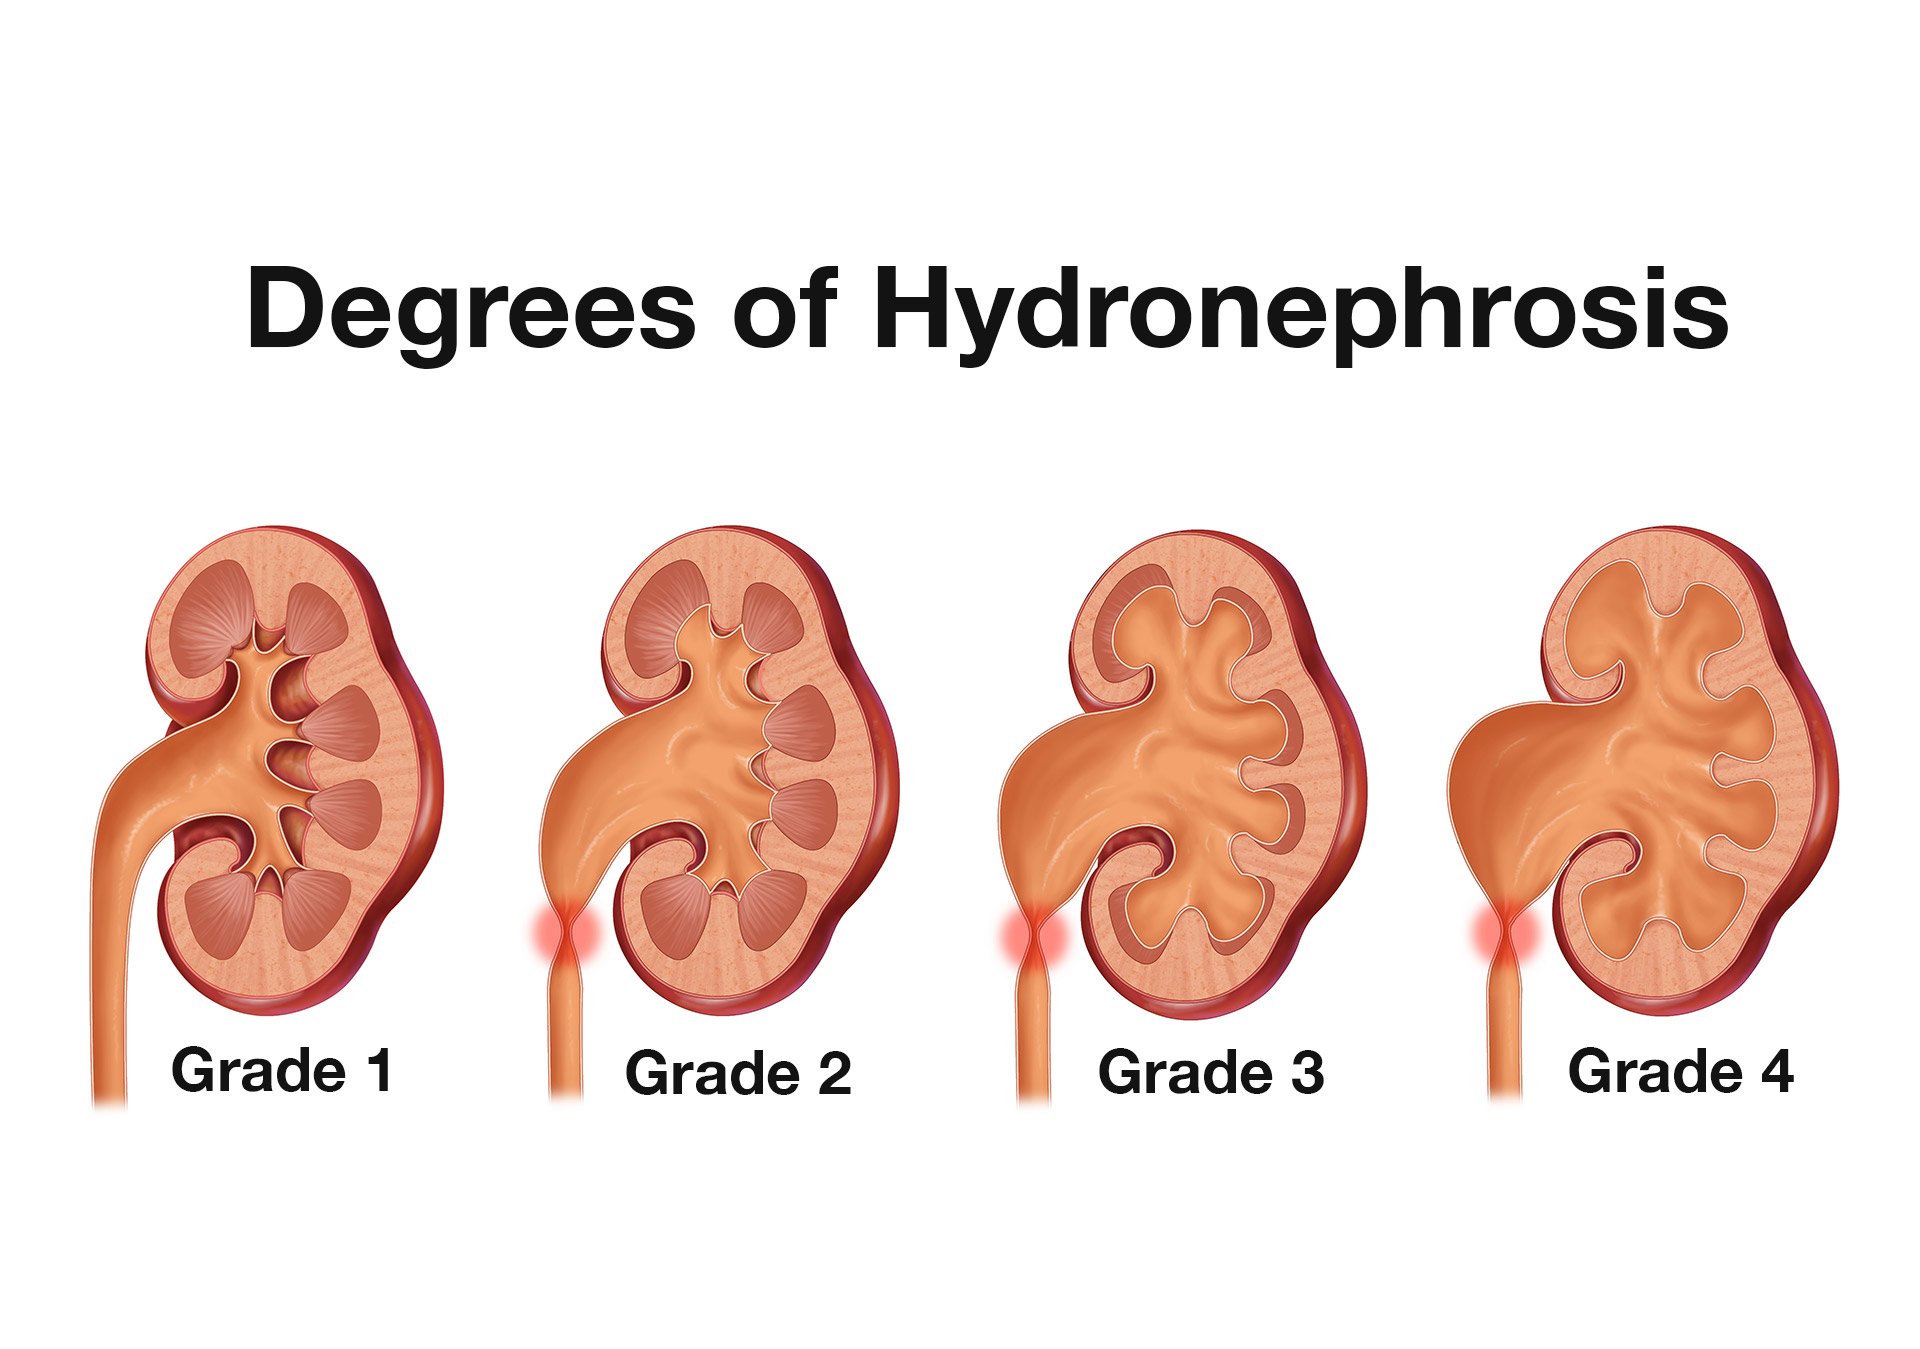

- The primary sonographic abnormality you will identify in the patient with suspected renal colic is hydronephrosis. The degree of hydronephrosis relates to the degree and extent of obstruction: (Illustration 2, Videos 11-17)

- After complete obstruction to flow, there is an acute rise in intrarenal pressure. The renal pelvis and calyces dilate first. On US you will see echo-free areas distending the normal bright (echogenic) central area of the kidney.

- As obstruction continues, the renal parenchyma becomes compressed and you see thinning of the pyramids.

- Illustration 2. Overview of degrees of hydronephrosis